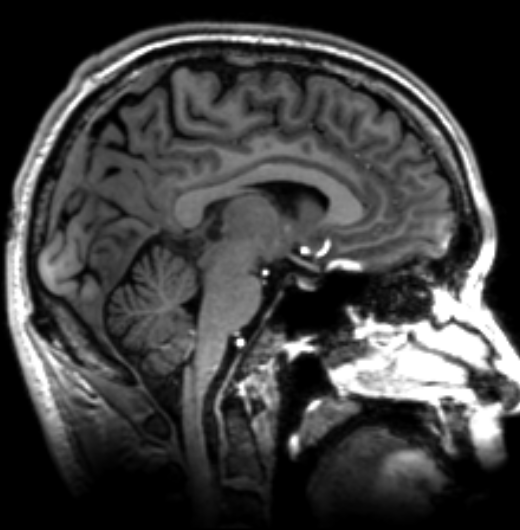

3/ Brain and cervical MRI were normal. Nerve conduction/EMG were normal. It wasn’t clear what was causing my symptoms, but at least we are ruled out a lot of scary possibilities. We settled on a wait-and-see approach.